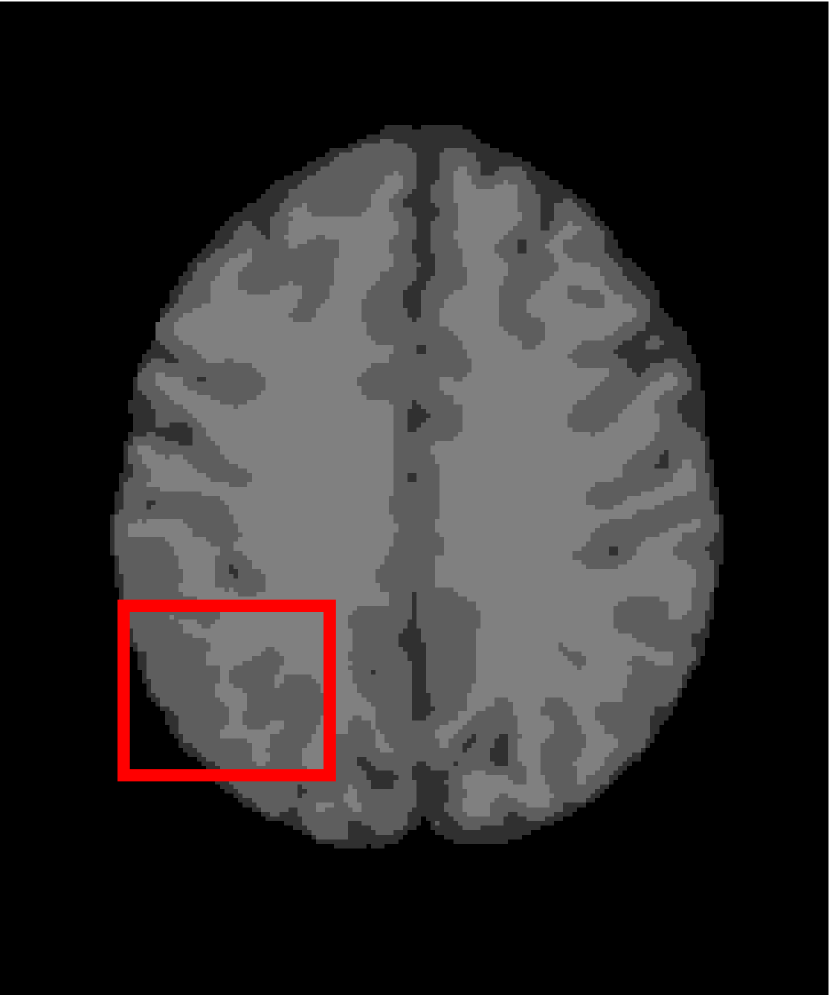

Next, we representatively segment five medical images from BrianWeb. They are represented as five slices in the axial plane with a sequence of 70, 80, 90, 100 and 110, which are generated by T1 modality with slice thickness of 1mm resolution, 9% noise and 20% intensity non-uniformity. Here, we set c=4𝑐4c=4 for all cases. The comparison between WRFCM and its peers are shown in Fig. 9 and Table II. The best values are in bold.

Figure 9: Segmentation results on five medical images. The parameter: ϕ=5.35italic-ϕ5.35\phi=5.35. From top to bottom: noisy images, ground truth, and results of FCM_S1, FCM_S2, FLICM, KWFLICM, FRFCM, WFCM, DSFCM_N, and WRFCM.

By a view of the marked red square in Fig. 9, we find that FCM_S1, FCM_S2, FLICM, KWFLICM and DSFCM_N are vulnerable to noise and intensity non-uniformity. They give rise to the change of topological shapes to some extent. Unlike them, FRFCM and WFCM achieve sufficient noise removal. However, they produce overly smooth contours. Compared with its seven peers, WRFCM can not only suppress noise adequately but also acquire accurate contours. Moreover, it yields the visual result closer to ground truth than its peers. As Table II shows, WRFCM obtains optimal SA, SDS and MCC results for all five medical images. As a conclusion, it outperforms its peers visually and quantitatively.